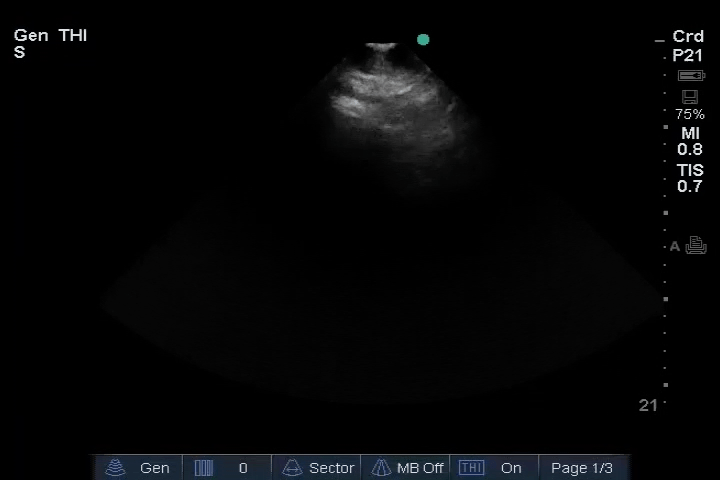

Heart: SC: Other cardiac views: Bad image

12_Heart_PLAX (normal)

13_Heart_PSAX (normal)